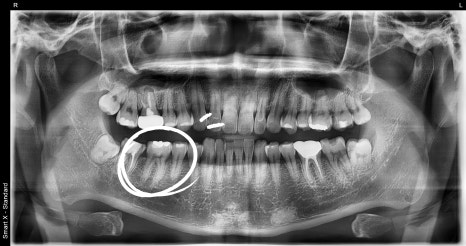

내원 당시 파노라마 사진 및 구강내 사진

파노라마 엑스레이 촬영을 통해

오른쪽 아래 첫 번째 어금니(제1대구치)에 깊은

충치가 진행되어 있는 상태를 확인했습니다.

다행히도 신경까지는 도달하지 않아 신경치료 없이

인레이 치료로 치아를 살릴 수 있는 상태였습니다.